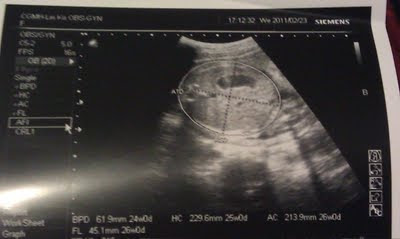

醫師是很好心的每次都會替Schumi照超音波看一下Schumi心臟,頭圍,四肢 還有體重等等

只是...我每次都看不太懂超音波的畫面..(可能我太沒有想像力了吧??) 但頭和心臟我看得出來

(這一張是大腿骨)